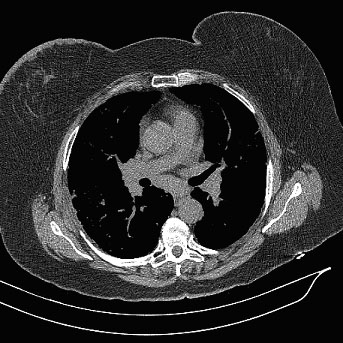

Chest CT: Multiple nodules smaller than a centimeter in diameter were present in both lungs with a perilymphatic distribution. A right paratracheal lymph node measured 1.9 cm. There was a 1.3 cm right precarinal lymph node, a 1.4 cm left anterior mediastinal lymph node, and a 1.4 cm subcarinal lymph node as well. There was no pleural effusion or pneumothorax (Figures 1 and 2).

Figure 2. Axial view of high-resolution chest CT using mediastinal windows showing bilateral hilar and subcarinal lymphadenopathy.